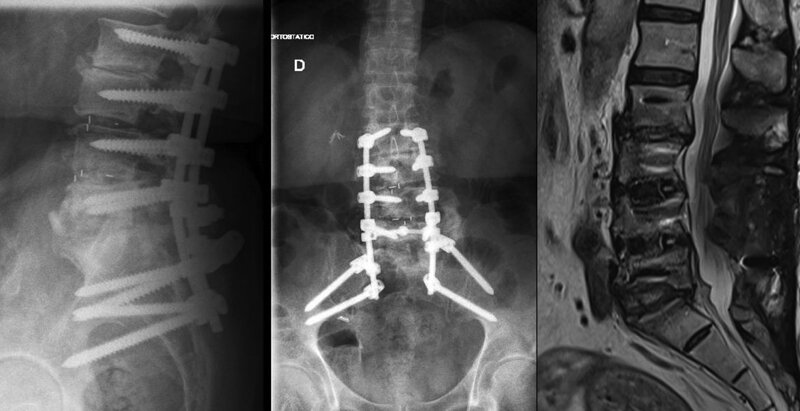

Na ressonância magnética, as sequências T2 e T2* têm objetivos diferentes. O T2 tradicional (Spin Echo ou FSE) destaca estruturas com alto teor de água, como o líquido cefalorraquidiano, edema e inflamações. Já o T2* (Gradient Echo ou SWI) é extremamente sensível a variações de campo magnético, como sangue, calcificações e metais.

- Uso comum: Edema cerebral, abcessos, tumores, lesões medulares.

- Vantagem: Alta qualidade de imagem e menos artefatos de suscetibilidade.